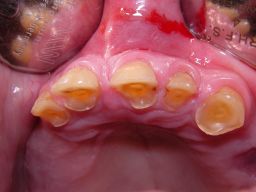

Das Hauptproblem dieses Falles lag im Oberkiefer - die über die Jahrzehnte abgeknirschten, kurzen Zähne erschweren Kronen, die durch eine Prothese belastet werden können. Die gewählte Lösung besteht darin, die Zähne nur rundherum zu beschleifen, aber nicht mehr zu kürzen und die Prothese mit einem Druckknopfsystem an die Zähne anzukoppeln, das ein "Spiel" aufweist, so daß die Prothese nicht als Hebelarm auf die schwachen Restzähne wirken kann. Rechts die beschliffenen Zähne kurz vorm Zementieren der Kronen.

Oberkieferrestzähne von vorne

Oberkieferrestzähne in Aufsicht

Oberkiefer vorm Zementieren

Oberkiefer von innen